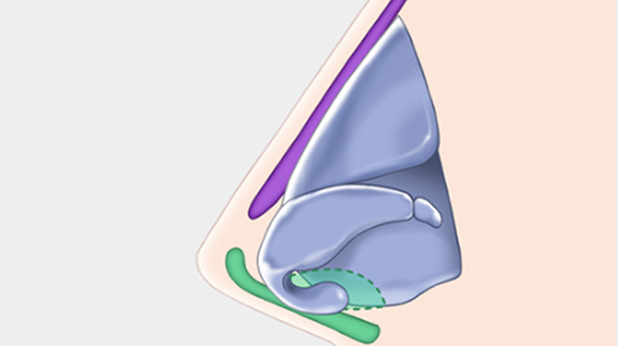

在精確的診斷基礎上, 指定精準的手術計劃